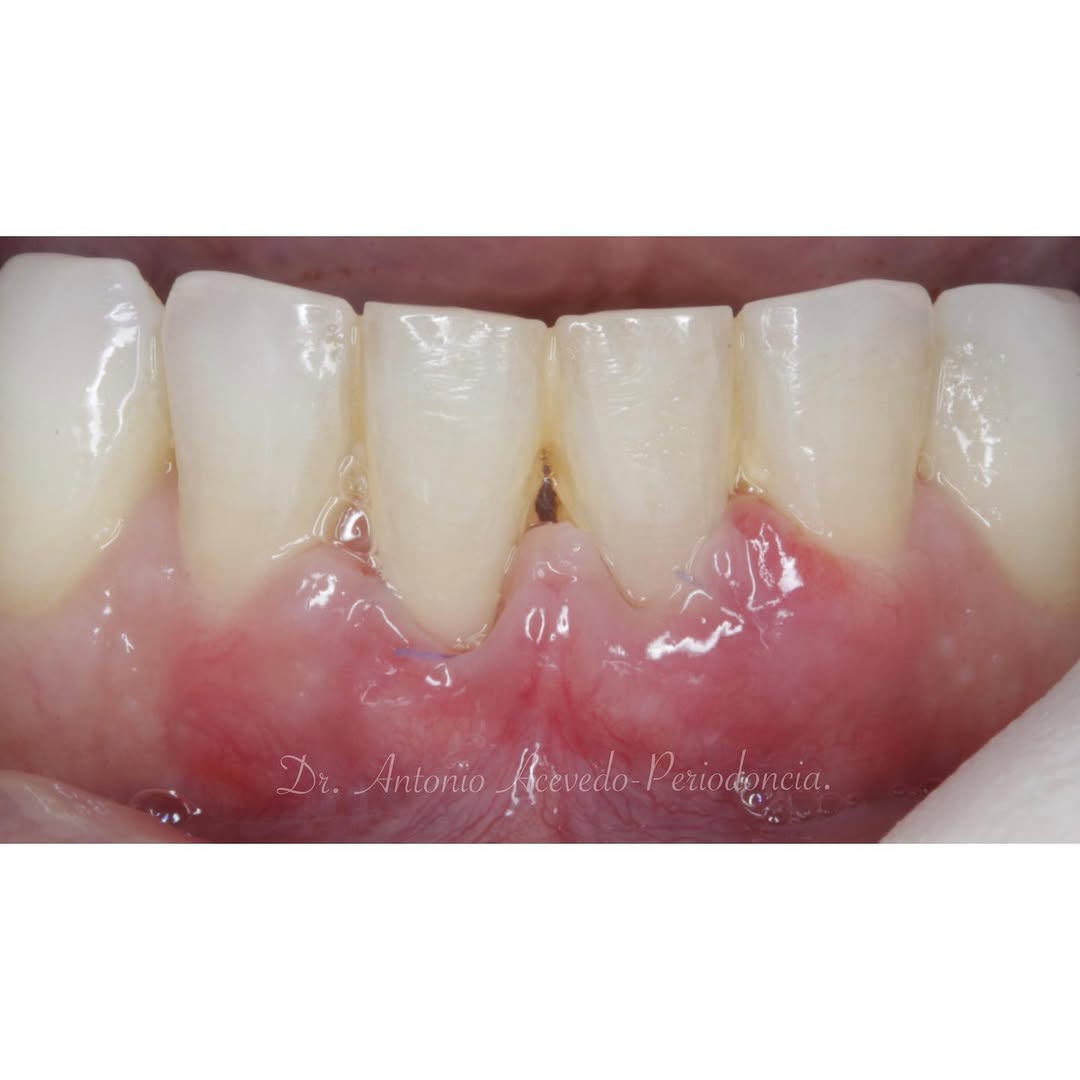

Hoy en día la Periodoncia es una de las áreas más importantes de la Odontología. En nuestro Centro de Formación te brindamos las mejores herramientas educativas y de capacitación necesarias para obtener el mayor provecho en el campo de la Odontología Estética y Restaurativa.

El objetivo del

Los problemas estéticos de una sonrisa no se ciñen sólo a los dientes eso lo sabemos todos. Por eso un curso de Perio-Estética, es fundamental para poder abordar casos de Estética y solo a través de un correcto diagnóstico previo podremos realizar un adecuado plan de tratamiento, muchas